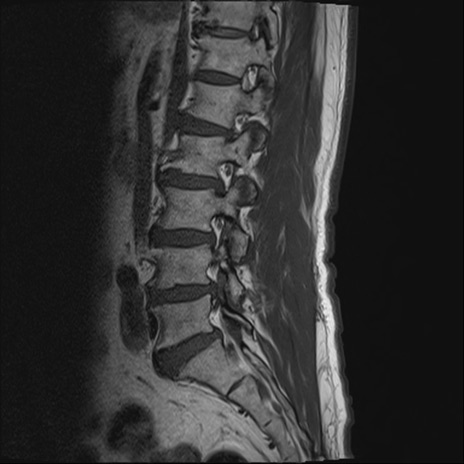

【整形】TIPS症例2 腰椎MRI T1WI(矢状断像)

【症例】70歳代男性

【主訴】左下肢痛

【現病歴】2週間前くらいから腰痛、左下肢痛あり。左臀部から大腿、下腿外側のしびれが常時ある。歩行とともに同部位の痛みあり。

【身体所見】Lasegue70-/60+、Bragard-/±、PTR ±/±、ATR -/-、IP 5/5、TA 5/4、TS 5/5、EHL 右第1足趾なし/3、FHL 5/5、hypersthesia(-)、足背動脈触知良好

異常所見と診断は?